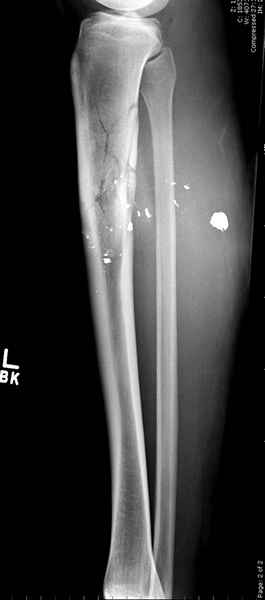

Здесь несколько примеров из нашей практики:

1 неполный перелом большеберцовой кости перкутанная пластина